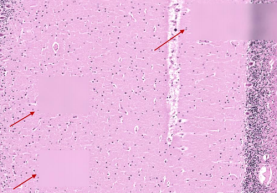

Problem: There are large out-of-focus areas in the image, most likely because there were not enough focus sites.

Problem: There are out-of-focus tiles dispersed throughout an otherwise in-focus image. In our experience, this occurs with extremely “wavy” tissue with drastic differences in z-depth between focus sites. The focus map interpolation cannot account for these large differences resulting in out-of-focus tiles.